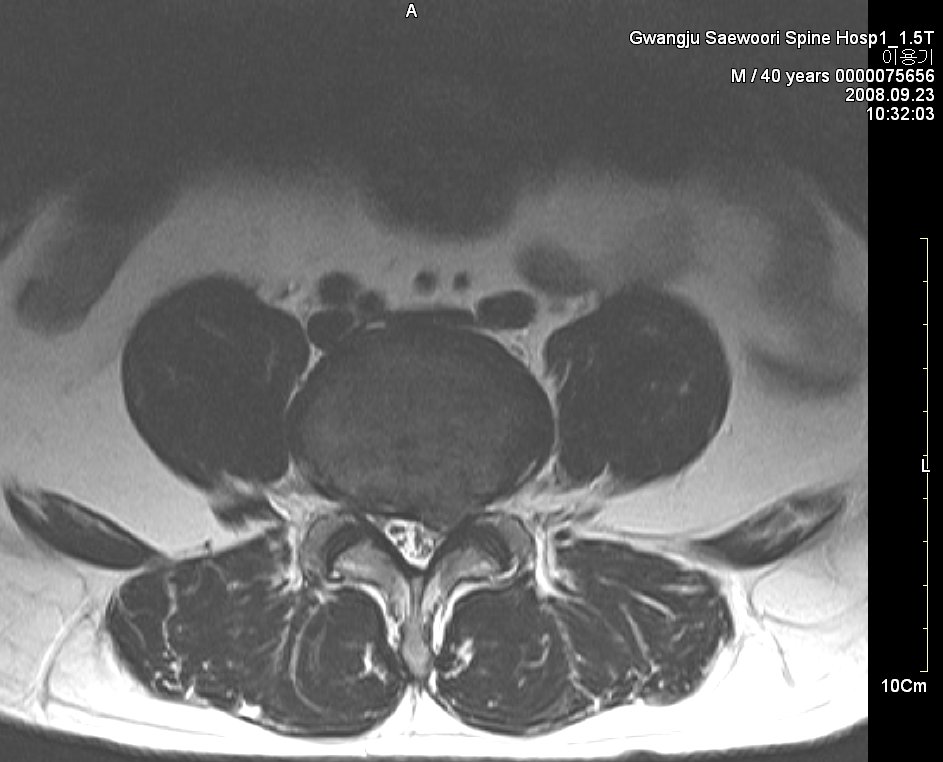

그림. sequestration사진. 월산동 남편 mri

그림. 흡수된 사진

symptom : local low back pain, lt buttock pain, lt leg radiating pain 허리에서 엉덩이 종아리까지 쑤시고 애림. 야간에는 통증으로 잠을 못 이룸.

sign : l5 sensory impairment, motor nerve intact(manual muscle powr test - nonspecific), dtr(++/++)

evidence : l-spine mri 사진

치료과정

침상안정 3일, 3일동안 허리 얼음찜질 1시간 30분씩 하루 5회 시행,

제가 2년 전 월산원광한방병원에서 치료한 환자 사진입니다. 수술을 위주로 치료하는 의사가 판단하기에 황당하게 보일지 모르겠습니다. 하지만 이 환자는 현재 가끔 골프도 치면서 허리디스크를 앓기 전보다 더 건강한 허리를 가지고 살아가고 있습니다.